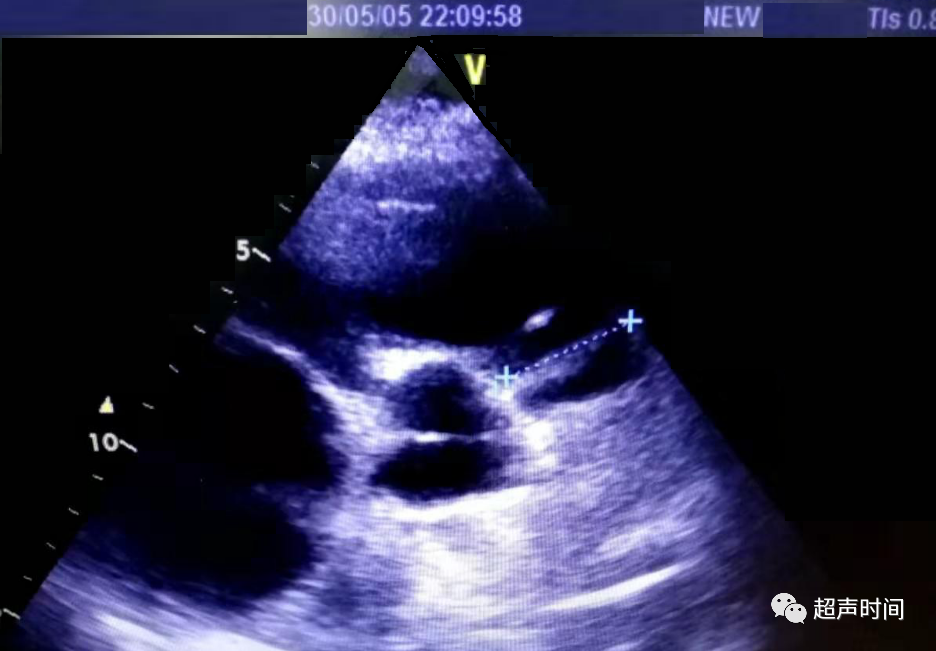

急诊床旁心脏超声所见如下:

图 3 和图 4 大动脉短轴切面显示右心房右心室增大,肺动脉扩张,左心室呈 D 型,充盈受限